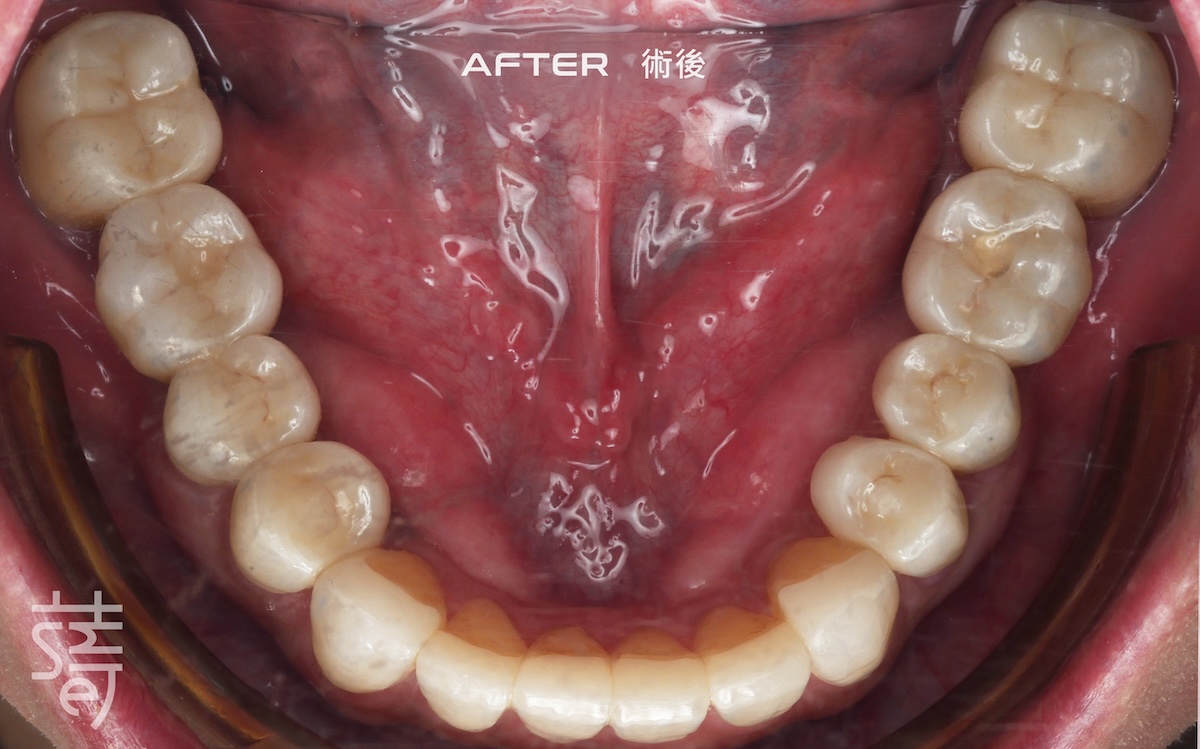

經過一段完整而細緻的治療,李先生終於重新露出久違的笑容,自然、上鏡,也能自在享受每一口美食。

After a thorough and meticulous treatment, Mr. Li finally revealed a long-lost smile—natural, camera-ready, and able to enjoy every bite with ease.

從矯正、植牙、臨時假牙的調整,到最終假牙的完成,每一步都凝聚著薛醫師的專注與團隊的細心。透過 Modjaw 的動態咬合紀錄與國際專家的臨床經驗,蒔美讓李先生的笑容不只漂亮,更兼具穩定與健康。

From alignment, implants, and temporary prosthetic adjustments to the final restoration, every step reflected Dr. Xue’s focus and the team’s care. With Modjaw’s dynamic bite records and international expertise, Smile ensured Mr. Li’s smile was not only beautiful but stable and healthy.